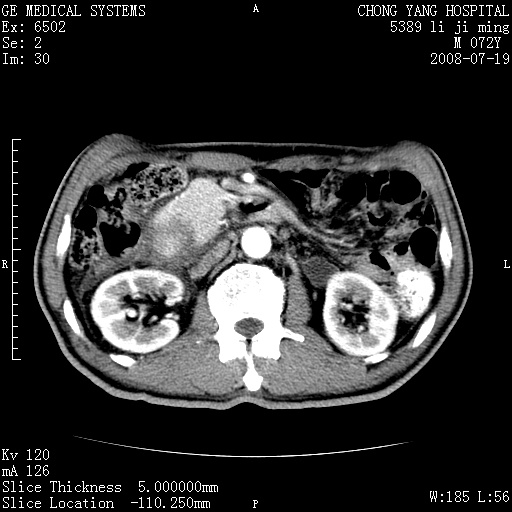

以下是引用zjzjr在2008-7-19 20:57:00的发言:[br]胰头增大,边缘模糊,周围可见渗出影,右侧肾前筋膜增厚.支持胰腺炎.

以下是引用yangyudong333在2008-7-20 6:56:00的发言:[br]胰腺增大尤以胰头明显,边缘模糊,周围可见渗出影,右侧肾前筋膜增厚,肠管於涨.支持胰腺炎

以下是引用不学无术在2008-7-19 23:15:00的发言:[br]胰腺增大尤以胰头明显,边缘模糊,周围可见渗出影,右侧肾前筋膜增厚,肠管於涨.支持胰腺炎